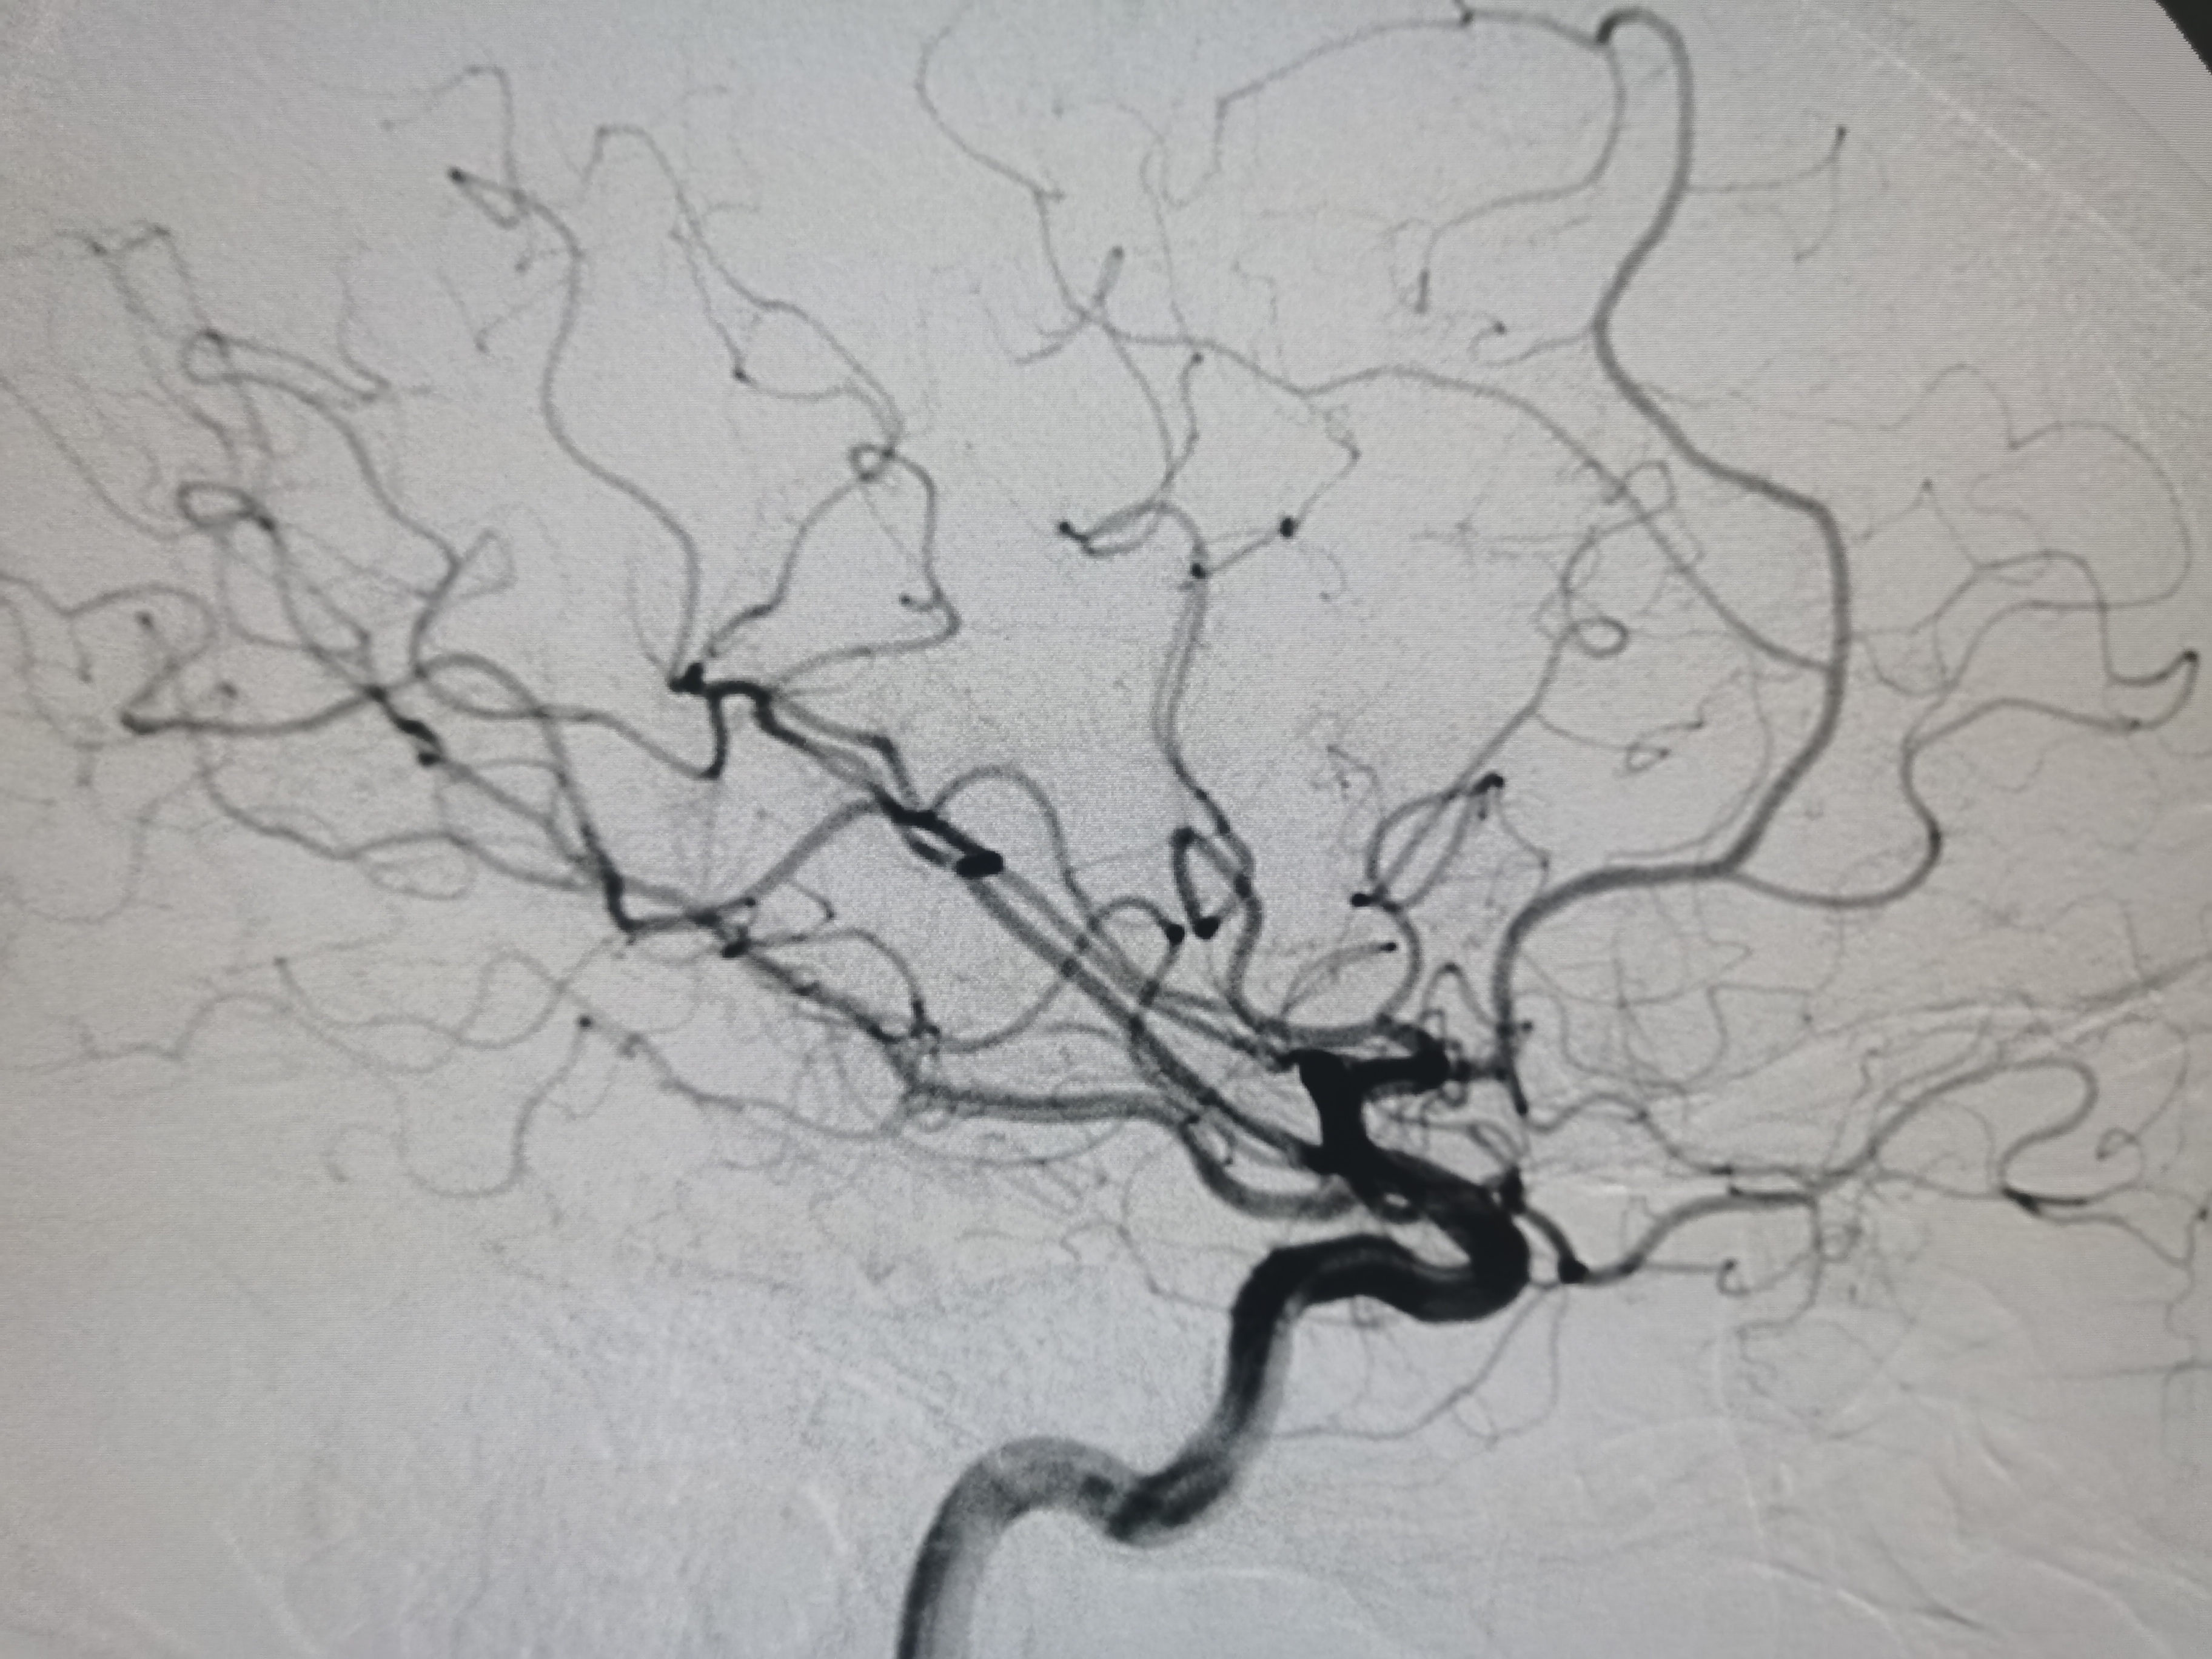

右侧颈内动脉正常。

左侧颈内动脉起始部正常。

左侧大脑中动脉闭塞,胚胎型大脑后动脉。

动脉晚期可见软膜支代偿远端血供。

8F导引导管及中间导管迅速建立通路,微导丝携微导管顺利通过病变。

微导管确认位于真腔。

4/20取栓支架释放后血管再通。

SWIM技术取栓一次,取出的血栓。

取栓后颅内血管再通,血流通畅。

患者穿刺到再通15分钟,术后颅内血流通畅,TICI3级,撤出各级导管结束手术。继续内科药物治疗,观察病情。

2、本例患者路径良好,快速建立通路,SWIM技术取栓一次,完全再通。